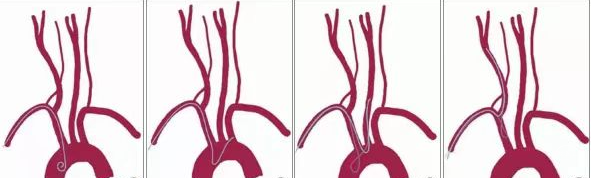

经绕动脉可能完成的颈内动脉介入通路建立。

1、右侧颈总动脉开口在双侧锁骨下动脉高点与主动脉弓两条平行线的二分之一以上,血管成角相对大,导管容易超选到位。(下图1)

2、左侧颈内动脉与右侧无名动脉成角大于45°,导管容易超选到位(下图2)。

经绕动脉完成右侧颈内动脉介入通路建立示意图

1、经绕动脉完成的左侧颈内动脉介入通路建立示意图

3、经绕动脉完成的牛型颈内动脉介入通路建立示意图

经绕动脉完成牛型颈内动脉介入通路建立示意图